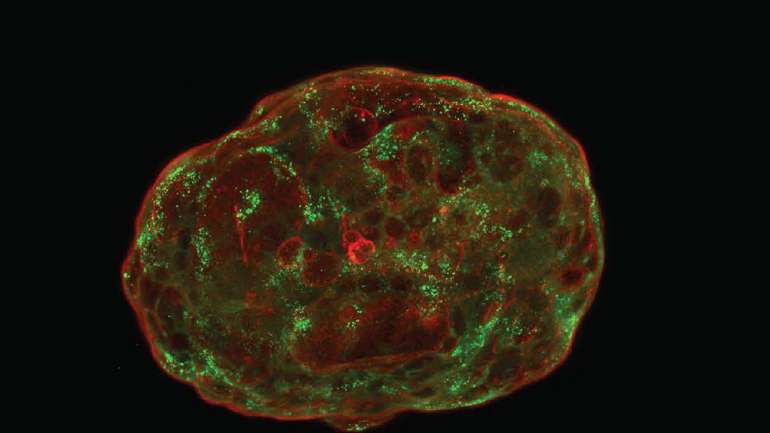

Вирощені зі стовбурових клітин імітаційні ембріони повторюють розвиток після стадії імплантації.

Біологи, які намагаються створити лабораторні моделі раннього росту людського ембріона, зробили серйозний крок вперед. Чотири дослідницькі групи повідомили про використання різних видів людських стовбурових клітин, деякі з яких генетично модифіковані, для створення ерзац-ембріонів, які нагадують справжні ембріони віком до 14 днів, відтворюючи період розвитку людини, який дуже важко вивчати.

«Подібність до природного ембріона дивовижна», — говорить біолог розвитку Джессі Венвліт з Інституту молекулярної клітинної біології та генетики імені Макса Планка про імітацію ембріона з лабораторії під керівництвом біолога зі стовбурових клітин Джейкоба Ханни з Інституту науки Вейцмана.